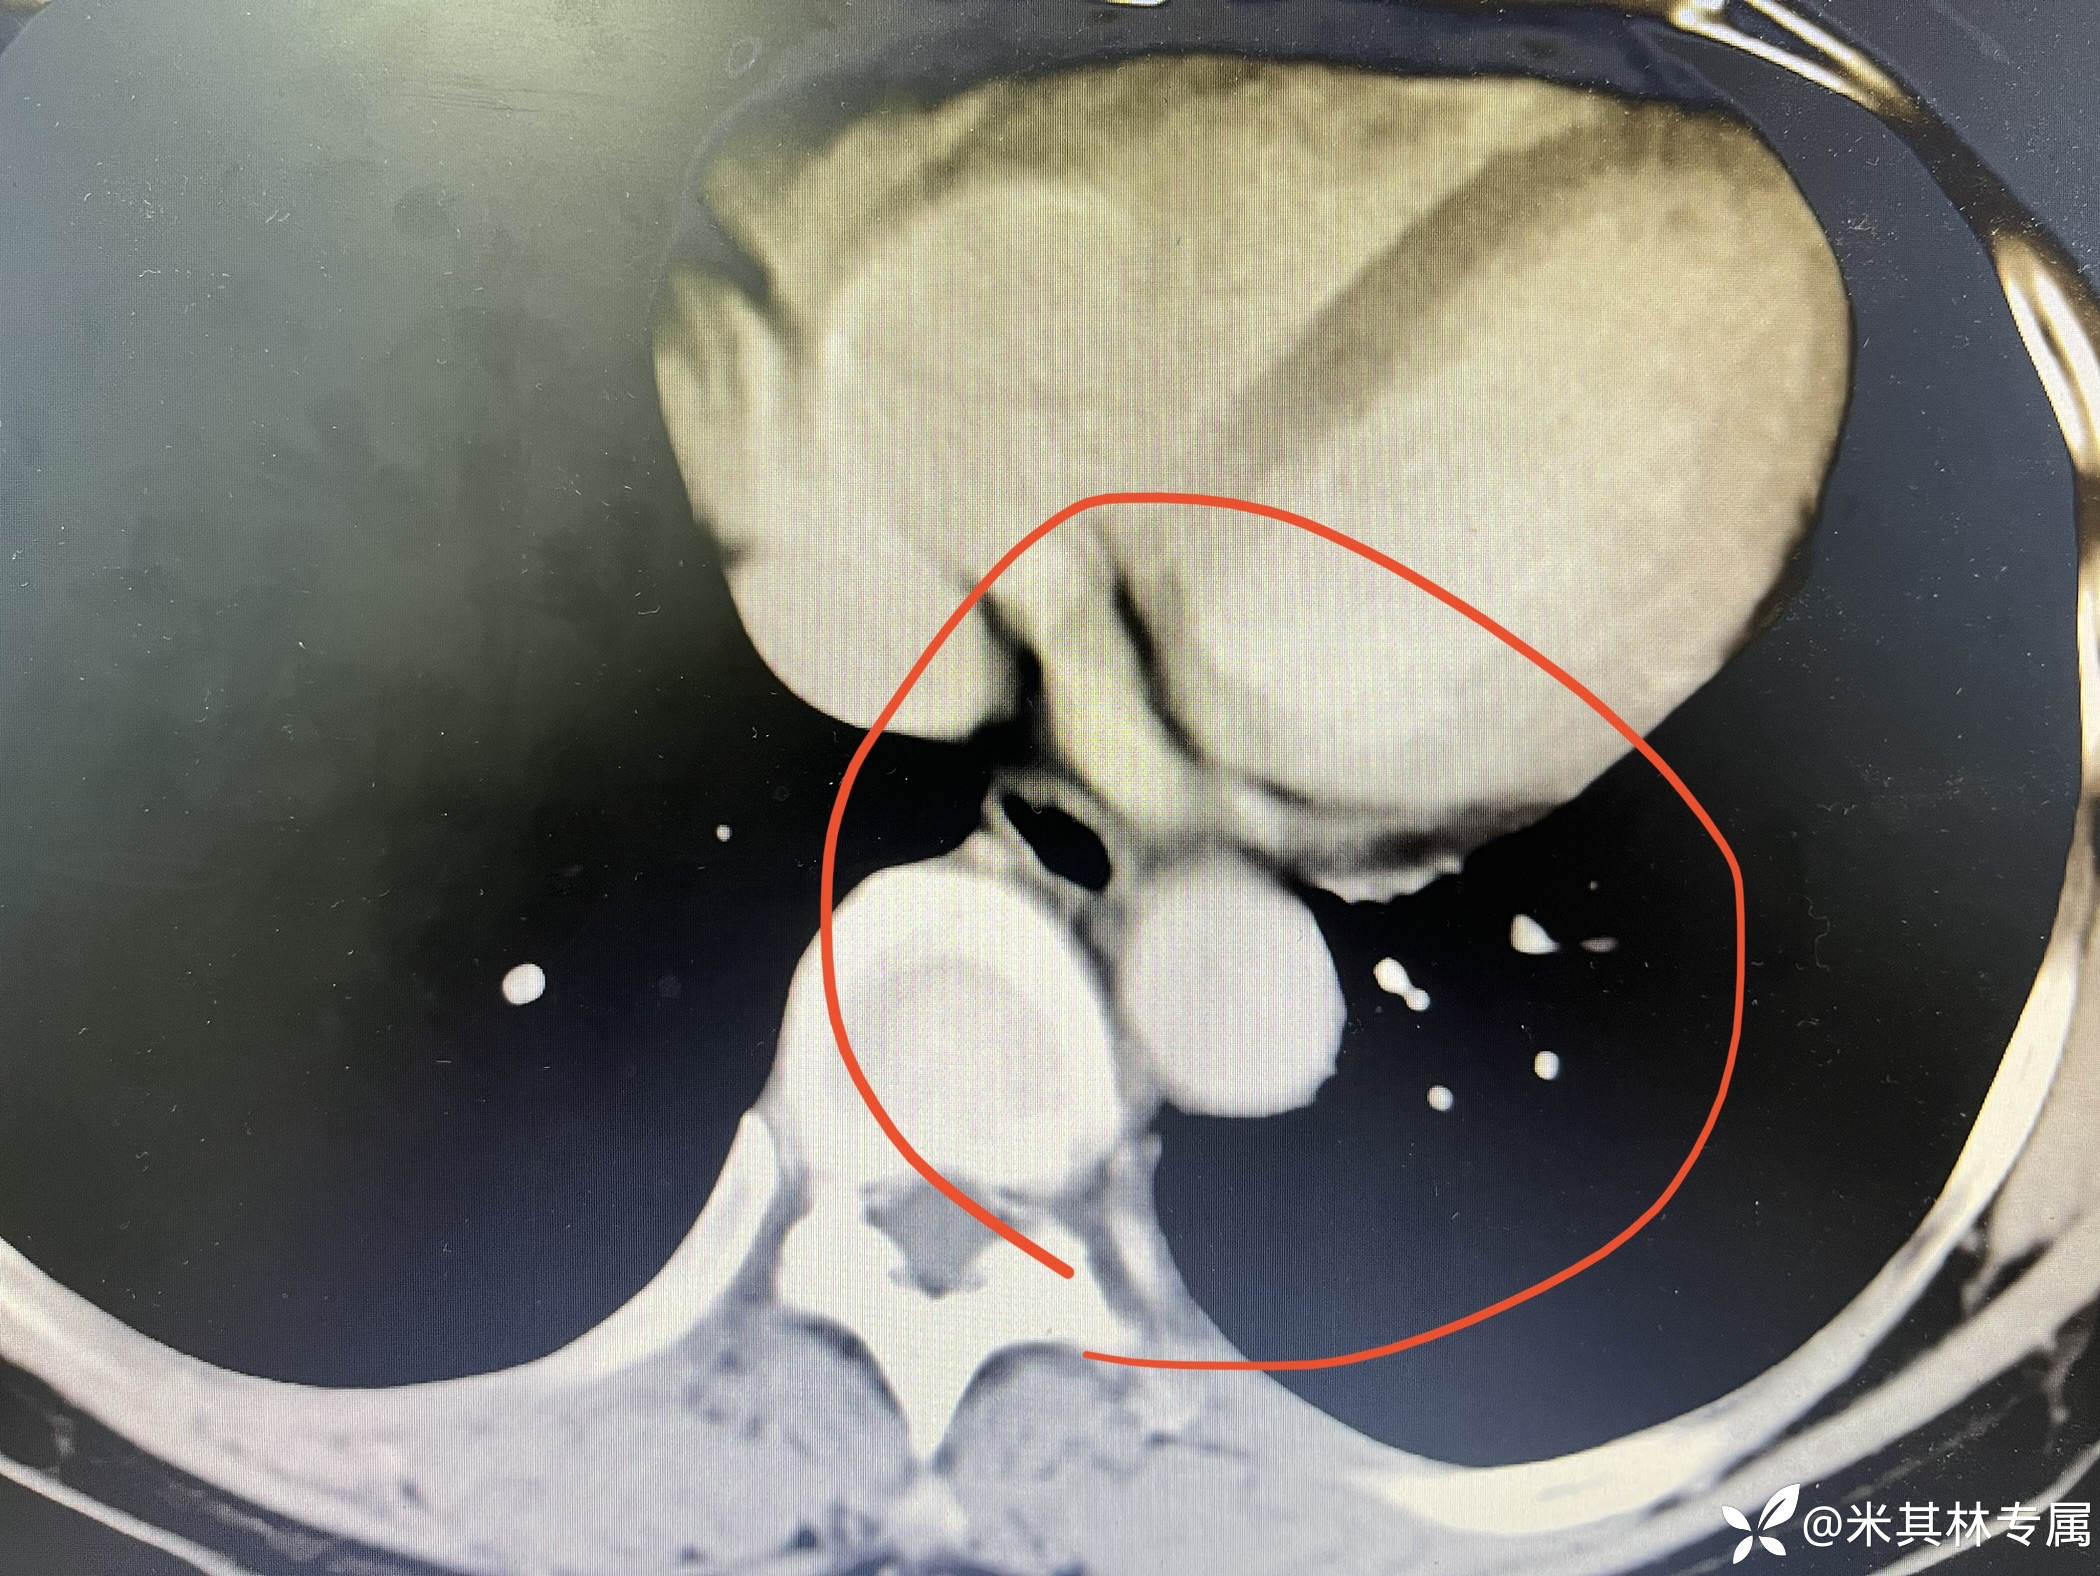

患者2023-09-09我院门诊胸部肺ACTA示:两肺肺动脉及其分支内未见明显血栓形成征象;左肺下叶近肺底处团片影,肺隔离征?;两肺散在肺气囊。左肺上下叶小斑点,右肺上叶胸膜下小斑点灶;两侧胸膜局部稍增厚。

临床诊断:肺部阴影:肺隔离征,原发性高血压